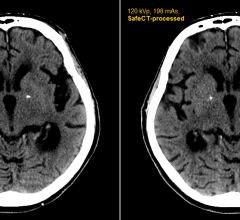

April 16, 2012 — Medic Vision Imaging Solutions Ltd. announced that within six months of clinical use in the United States, its SafeCT image enhancement system has delivered diagnostic image quality to more than 20,000 CT (computed tomography) studies acquired with low-dose protocols.